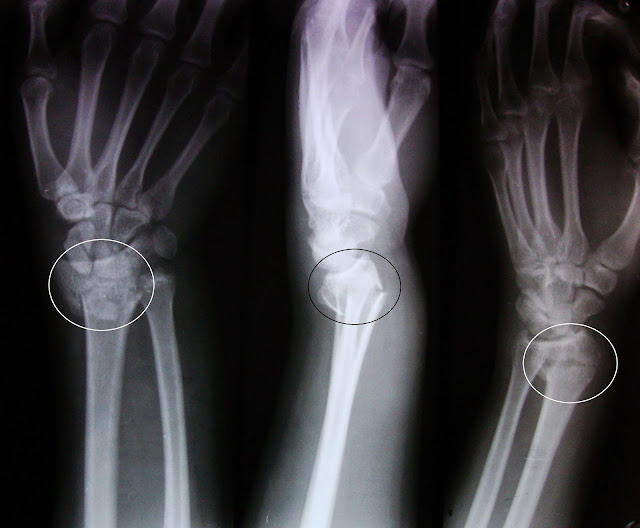

Το κάταγμα Colles αποτελεί ένα από τα πιο γνωστά κατάγματα του χεριού. Πρόκειται για εγκάρσιο κάταγμα της κερκίδας, περίπου 20-35 εκατοστά από την πηχεοκαρπική άρθρωση. Το κάταγμα του κάτω πέρατος της κερκίδας περιγράφηκε πρώτη φορά το 1814 από τον Abraham Colles, προς τιμή του οποίου πλέον αναφέρεται ως «Κάταγμα Colles». Ο Abraham Colles (1773 – 1843) περιέγραψε το κάταγμα αυτό ως εξής: Ήταν κοντά στην άρθρωση του καρπού, σε απόσταση έως 2.5cm από αυτή. Συνοδευόταν από κάταγμα της στυλοειδούς απόφυσης της ωλένης και εμφάνιζε ραχιαία μετατόπιση του περιφερικού τμήματος. Συνήθως συμβαίνει μετά από πτώση στην παλάμη με το χέρι να βρίσκεται σε έκταση (τεντωμένο). Χαρακτηρίζεται από ραχιαία και κερκιδική παρεκτόπιση του περιφερικού τμήματος με ταυτόχρονη κλίση της αρθρικής επιφάνειας της κερκίδας προς τα άνω (ραχιαία), ενώ φυσιολογικά έχει κλίση ελαφρά προς τα κάτω (παλαμιαία).Ο ασθενής παρουσιάζει πόνο, τοπικό οίδημα, αδυναμία στις κινήσεις της πηχεοκαρπικής. Το κάταγμα αυτό, προκαλεί χαρακτηριστική παραμόρφωση του χεριού που παίρνει το σχήμα πιρουνιού. Είναι συχνότερο σε μεσήλικες και υπερήλικες.- Ακόμη συχνότερο σε γυναίκες που πάσχουν από οστεοπόρωση.Πώς γίνεται η διάγνωση; Ψηλαφούμε με τα δάκτυλά μας το οστούν της κερκίδος πάνω από τον καρπό (η κερκίδα είναι το οστούν που βρίσκεται στην ευθεία του αντίχειρα-το άλλο οστούν, η ωλένη βρίσκεται στην ευθεία του μικρού δακτύλου). Ξεκινάμε κάτω από τον αγκώνα ψηλαφώντας το κόκκαλο. Το κάταγμα είναι ευαίσθητο όταν πλησιάσουμε 2-3 δάκτυλα πριν από τον καρπό. Το άλλο σημείο που καθιστά βέβαιη τη διάγνωση του κατάγματος, είναι ο μεγάλος περιορισμός των κινήσεων του καρπού (σύγκριση με το υγιές) που είναι σε 90ο κάμψη και έκταση της παλάμης. Μεταφορά στον γιατρόΧρειάζεται ιατρική φροντίδα από ορθοπαιδικό. Μέχρι να φτάσουμε σε νοσοκομείο, τοποθετούμε ένα πρόχειρο νάρθηκα. Καλύπτουμε το χέρι (καρπό) με βαμβάκι, μέχρι τη μέση της παλάμης και τη μέση του αντιβραχίου. Τοποθετούμε δύο φύλλα από χαρτόνι στη ραχιαία επιφάνεια και παλαμιαία επιφάνεια του καρπού. Τα συγκρατούμε με ελαστικό επίδεσμο. Συμβουλεύουμε τον τραυματία να κρατάει το χέρι του ψηλά αφού το κρεμάσουμε σε ένα μαντήλι (να κοιτάει τον άλλο ώμο). Ακτινολογικά, παρουσιάζεται η παραμόρφωση που προαναφέρθηκε, ενώ σε αρκετές περιπτώσεις συνυπάρχει κάταγμα της στυλοειδούς απόφυσης της ωλένης. ΘεραπείαΣτα κατάγματα χωρίς παρεκτόπιση τοποθετείται γύψος για 3-4 εβδομάδες. Στα παρεκτοπισμένα κατάγματα Colles, η αντιμετώπιση στοχεύει στην κατά το δυνατόν ανατομική ανάταξη υπό τοπική αναισθησία, με αποκατάσταση του μήκους της κερκίδας και σωστό προσανατολισμό του περιφερικού τμήματος που περιλαμβάνει την αρθρική επιφάνεια. Η ακινητοποίηση σε γύψο γίνεται για διάστημα 5(πέντε) εβδομάδων περίπου, ενώ απαιτείται ακτινολογική παρακολούθηση κάθε 7(επτά) ημέρες για τις πρώτες 3(τρεις)